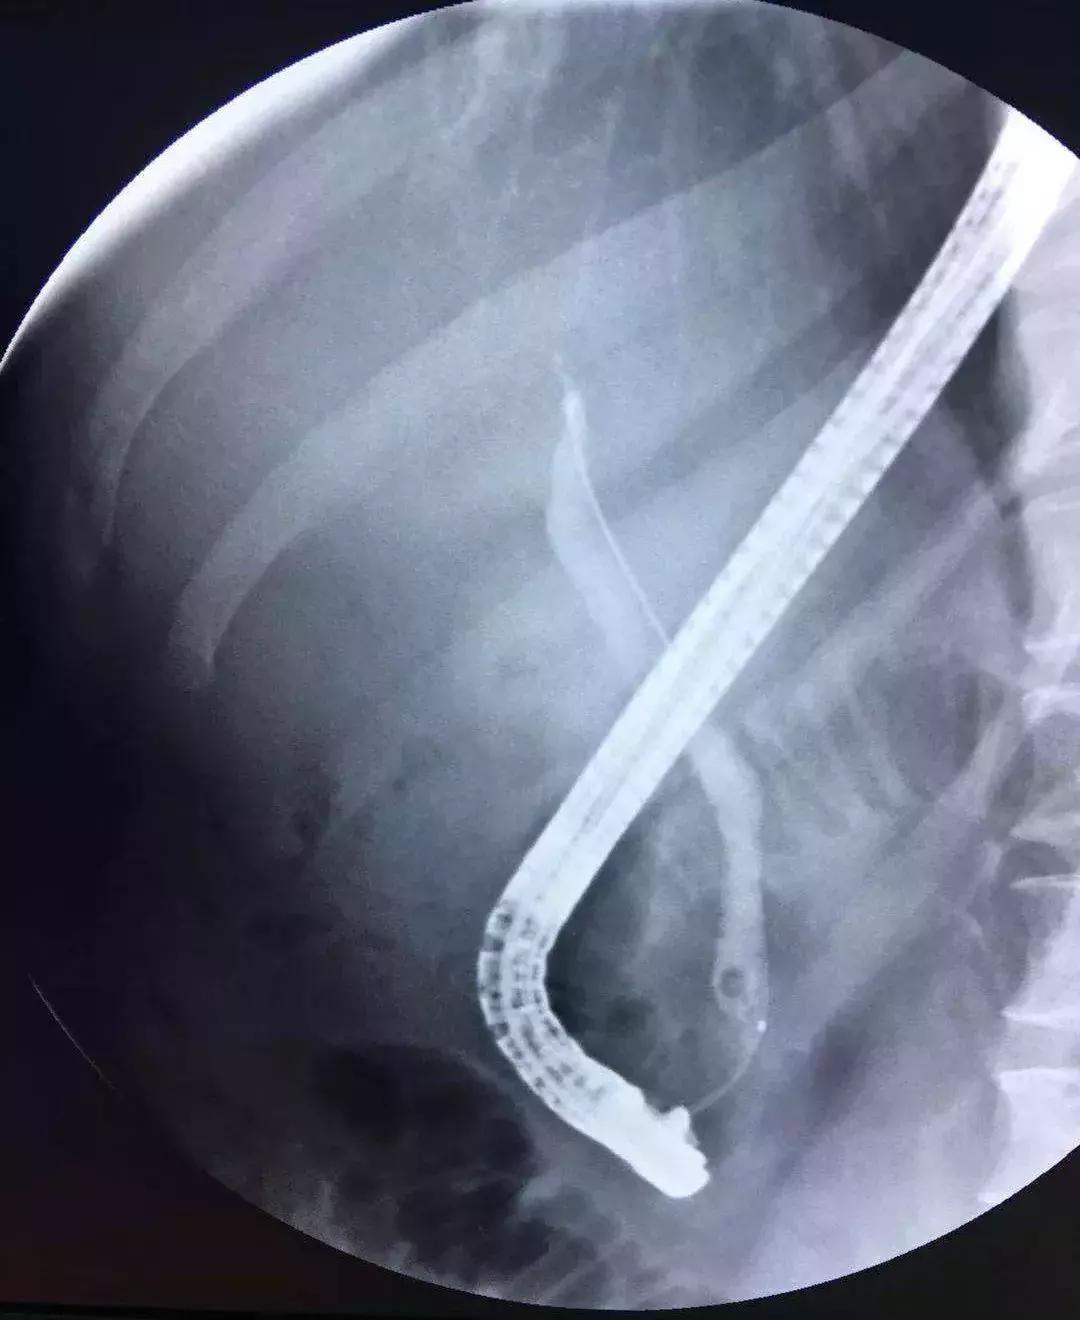

ERCP治疗

对于轻度或中度急性胆管炎伴胆管结石且无抗凝治疗或凝血功能异常的病人,可考虑在胆管引流的同时进行内镜下括约肌切开术(EST)清除结石,但EST常见的并发症有胰腺炎、十二指肠或胆管穿孔、出血和感染等,同时切开括约肌可能导致肠液返流,将来再次诱发胆管炎,因此有些医生选择气囊扩张壶腹部再行取石,这样能保留括约肌的功能。

对取石困难的病人,如结石较大或多发结石等,可以分两次进行:先行ENBD胆管引流,待炎症得到控制后再经内镜清除结石。